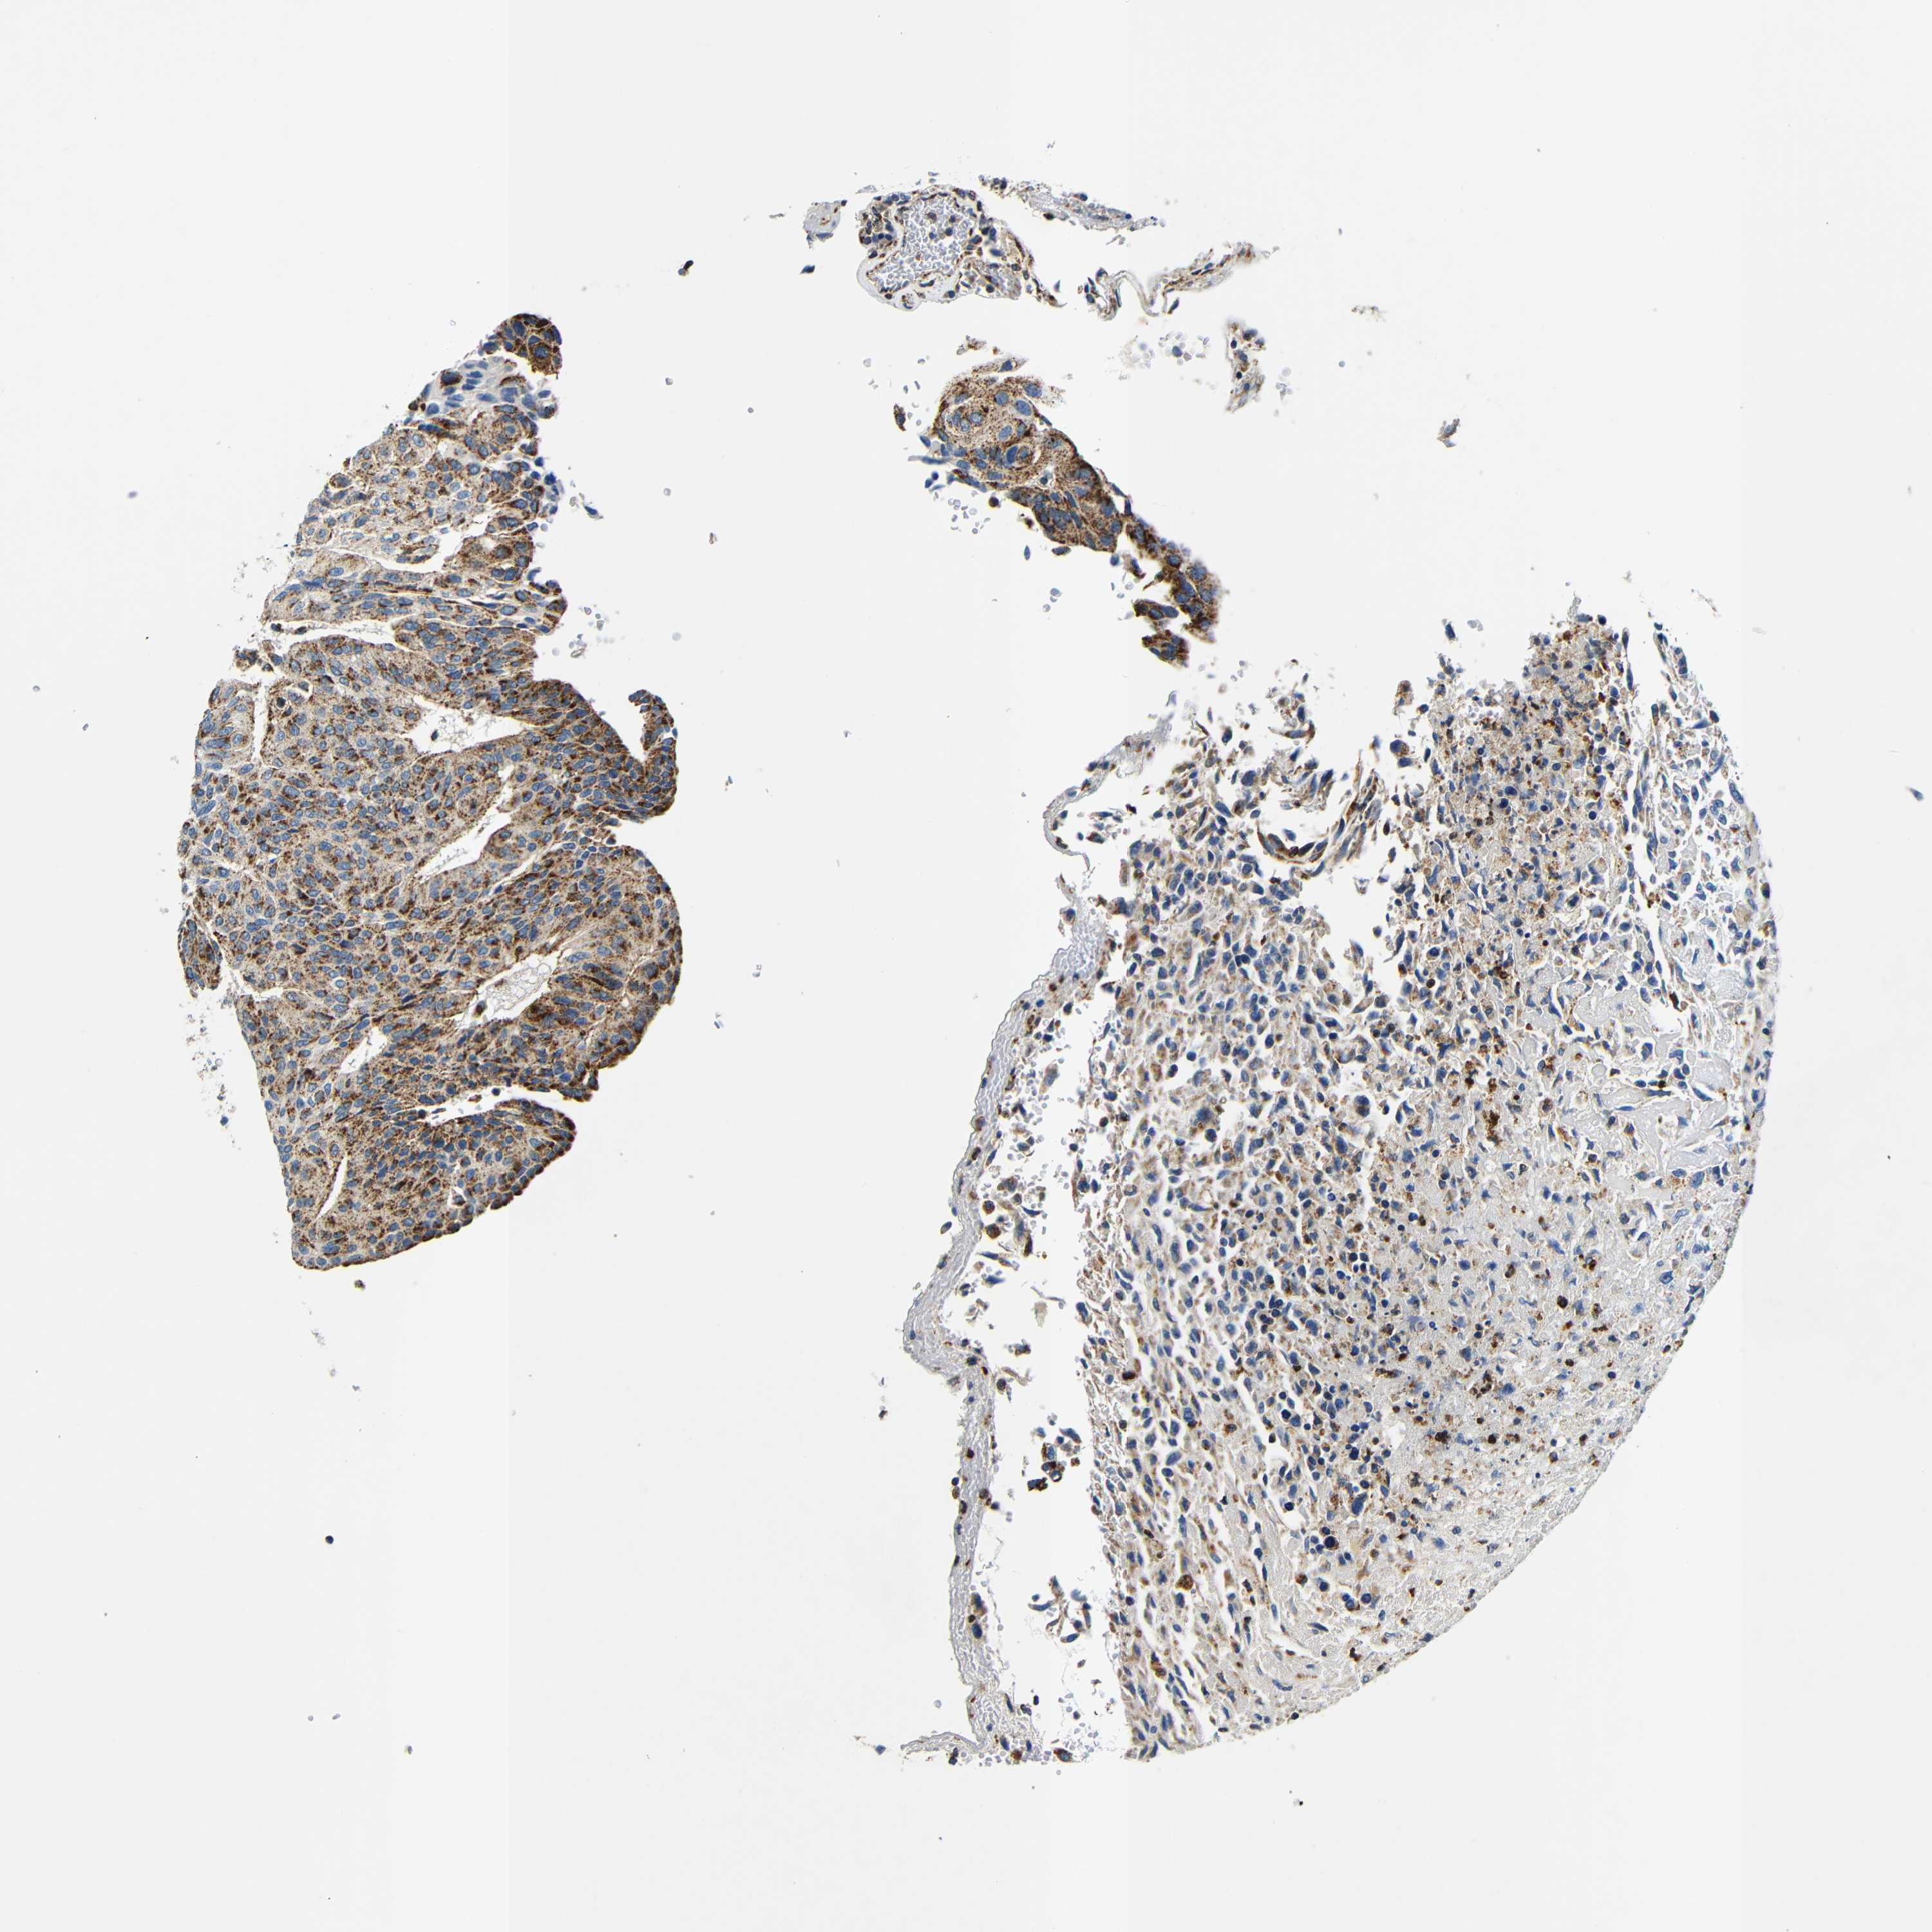

UROTHELIAL CANCER - Protein expressioni

A mouse-over function shows sample information and annotation data. Click on an image to view it in a full screen mode. Samples can be filtered based on level of antibody staining by selecting one or several of the following categories: high, medium, low and not detected. The assay and annotation is described here.

Note that samples used for immunohistochemistry by the Human Protein Atlas do not correspond to samples in the TCGA dataset.

Antibody stainingi

Antibody staining in the annotated cell types in the current human tissue is reported as not detected, low, medium, or high, based on conventional immunohistochemistry profiling in selected tissues. This score is based on the combination of the staining intensity and fraction of stained cells.

Each image is clickable and will lead to virtual microscopy that enables deeper exploration of all samples and also displays staining intensity scores, fraction scores and subcellular localization as well as patient and tissue information for each sample.

Antibody HPA012955

Staining

High

Medium

Low

Not detected

Intensity

Strong

Moderate

Weak

Negative

Quantity

>75%

75%-25%

<25%

None

Location

Nuclear

Cytoplasmic/membranous

Cytoplasmic/membranous,nuclear

Urothelial carcinoma, Low grade

Urothelial carcinoma, High grade